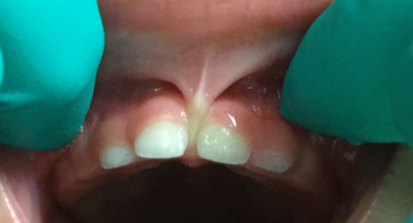

The lip tie was released on an 11 month infant.  One year later you can start to see the gap between the front teeth close. Although the tie was released for other issues, you can see the alignment of a child's front teeth change, especially if done before the canines erupt.